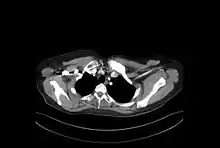

- 4)Hiperostose - Espessamento irregular do tecido ósseo subperiosteal

- 5)Osteíte inflamatória